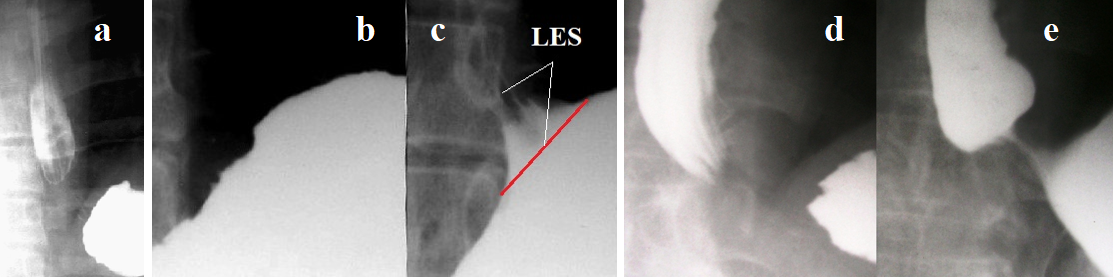

Belching and regurgitation (rumination syndrome) occur due to the opening of a weakened LES, which cannot withstand the tension due to increased pressure in the stomach after a meal or at any time after a relatively long contraction of the LES due to damage to the postural reflex. The reason for the erroneous idea that periodic relaxation of the LES is possible in healthy individuals is the same as for belching: as a control, patients with GERD with AET<4% were examined. This indicates that transient lower esophageal sphincter relaxation (TLESR) occurs because of damage to the function of the LES by hydrochloric acid and pepsin and cannot occur in healthy individuals. TLESR leads to reflux of gastric contents into the esophagus (liquid and gas), which is always damaged following the LES (Figure 5).

Figure 5. Comparison of radiographic examinations of the esophagus with their image on CT. (a). The patient could eat only liquid food. Belching and vomiting were often observed after meals. He refused to drink milk on the advice of a doctor. Then, immediately after a single intake of a milk drink, severe heartburn occurred, which confirmed lactose intolerance. The length of the LES, from the ampulla to the stomach, is equal to the height of D-10, i.e. about 2 cm, with the minimum normal limit of 3.2 cm. The ampulla is proximally closed by a pathological proximal sphincter (PS). The body of the esophagus from the PS to the aortic arch is in spasm with longitudinal folds and uneven fine-wavy contours. Above the aortic esophageal sphincter (AES), the esophagus dilated. (b). CT of the chest shows thickening of the esophageal wall (white line). (c). A patient with frequent belching and lactose intolerance, which he learned about at the age of 60. The length of the LES 1.4 cm is significantly shorter than the minimum normal limit of 3.2 cm. The esophagus sharply dilated along its entire length. (d). The CT shows a thickened and dense esophageal wall with uneven contours and a deformed perimeter of the ring (arrow). A similar picture observed in all CT sections, indicating fibrous changes in the esophageal wall. In fact, the wide esophagus was a fibrous sac with impaired peristalsis and constant gas throughout the entire length of the esophagus.

These data prove that belching is a symptom of GERD, which should be the basis for examination to start treatment to prevent further progression of GERD. Figure 6 shows the scheme of the pathological condition of EGJ in GERD, explaining the occurrence of belching.

Figure 6. (a). Radiograph of the left dome of the diaphragm of a healthy person. (b). A patient with GERD. (c). Scheme of the EGJ with normal LES function (red line is LES length). The angle of His (aH) is acute. Large gas bubble in the stomach. (d). In GERD, the LES is shortened because the intra-abdominal part of the LES (I-a) is not functioning. This leads to an increase in the angle of His and a decrease in the gas bubble of the stomach due to belching during transient relaxation of the weakened part of the LES.